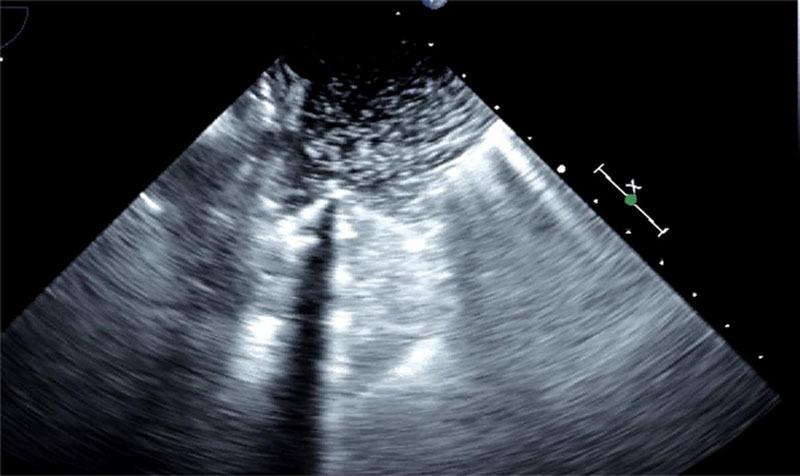

Bronchovenous fistula (BVF) associated with adult cardiac surgery is a rarely reported life-threatening condition. We present a 75-year-old woman who developed a BVF during cardiac surgery. Dense adhesion in the pleural and pericardial cavities was noted. Restrictive pulmonary pathology required high airway pressure. Transesophageal echocardiography and hemoglobin measurement were helpful for the timely diagnosis of BVF, which was controlled by transection of the right upper pulmonary vein where a vent catheter had been inserted. Injuries around the cannulated site presumably initiated the BVF, which was worsened by high-pressure ventilation. Therefore, cannulation site might be a risk factor for BVF.

与成人心脏手术相关的支气管静脉瘘(BVF)是一种罕见但危及生命的疾病。我们报告了一名75岁女性,她在心脏手术期间发生了BVF。术中发现胸膜腔和心包腔内有致密粘连。限制性肺部病变需要较高的气道压力。经食管超声心动图和血红蛋白测量有助于BVF的及时诊断,通过切断插入了通气导管的右上肺静脉来控制病情。插管部位周围的损伤可能引发了BVF,而高压通气使其恶化。因此,插管部位可能是BVF的一个危险因素。